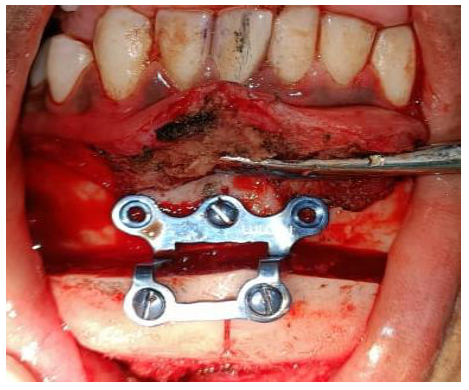

Markings for Advancement genioplasty were given over the lower labial mucosa. Advancement genioplasty with symmetry correction was performed to coincide with the dental and skeletal midline. A genioplasty plate of size 2 mm with five screws (2 mm × 10 mm each) was placed. A Romovac drain was placed over the left preauricular region. Closure was done in layers. Intraorally, the muscle and mucosa were sutured with 3-0 Vicryl, and extraorally, the muscle layer was sutured with 3-0 Vicryl and the skin layer with 4-0 Ethilon. Pressure dressing was given over the preauricular and chin region. The patient was advised to perform active mouth opening exercises postoperatively using a Hister jaw opener. The patient was discharged on postoperative day 10 with a mouth opening of approximately 18 mm (Figs. 4A-D and 5, respectively).

Advancement genioplasty and plating.